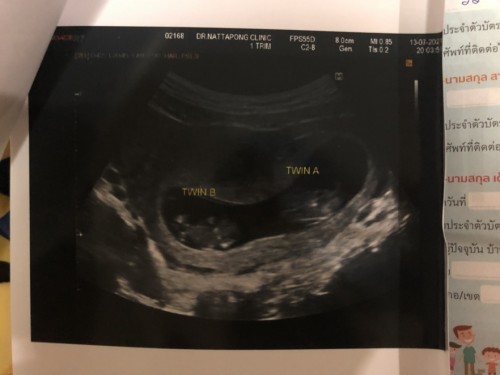

ครั้งนี้ท้องสองแล้วค่ะ แต่ความรู้สึกทุกอย่างไม่เหมือนท้องแรกสักนิด ตอนนี้ 10+6 w ค่ะ ท้องแรกเราไม่แพ้ท้องเลยสักนิด ใช้ชีวิตช่วงท้องได้แฮปปี้มากกินอะไรก็อร่อยไปหมด แต่ท้องรอบสองน้องเป็นแฝดค่ะ เราแพ้ท้องหนักมากกินอะไรไม่ได้เลย อาหารคิอกินได้ทีละ 4-5 คำก็จะอาเจียนแล้วค่ะฝืนกินต่อไม่ไหวจริงๆทรมาณมาก ตอนกลางวันก็เวียนหัวทั้งกินยาทั้งดมยาดมแทบตลอดเวลา รู้สึกใช้ชีวิตลำบากมากๆเลยค่ะ อดทนสุดๆอยากให้ผ่านไตรมาสแรกไปไวๆ ขอฟังประสบการณ์ของแม่ๆที่มีอาการแพ้ท้องหนักๆหน่อยได้มั้ยคะว่าผ่านมันไปยังไงบ้าง #ขอบคุณล่วงหน้านะคะ #ท้องแฝด